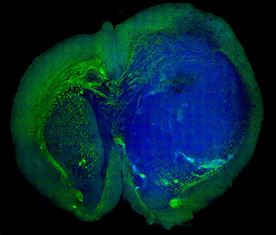

As the image shows, the technique can distinguish brain tumour from normal tissue with remarkable accuracy, by detecting the difference between the signal given off by the dense cellular structure of tumour tissue, and the normal healthy grey and white matter.

An image of a human glioblastoma brain tumour in the brain

of a mouse made with SRS microscopy. The tumor (blue)

is easily distinguished from normal tissue (green).